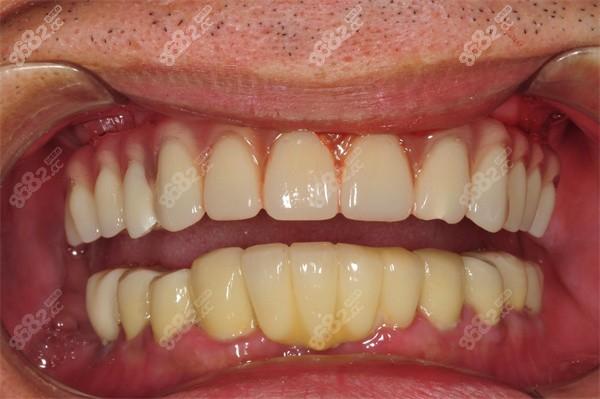

技术优势主要体现在五个方面:一是微创手术,仅需4个小切口,不翻瓣或小范围翻瓣,减少术后肿胀与疼痛;二是快速恢复,即刻负重让患者无需经历传统种植3-6个月的愈合期,即可正常进食;三是性价比高,种植体数量减少,手术与修复费用降低;四是功能与美观兼顾,牙桥材料采用高强度氧化锆或烤瓷,模拟天然牙形态与色泽,发音与咀嚼功能接近自然牙;五是长期稳定性,倾斜种植体增加骨接触面积,配合力学优化设计,10年成功率可达90%以上。